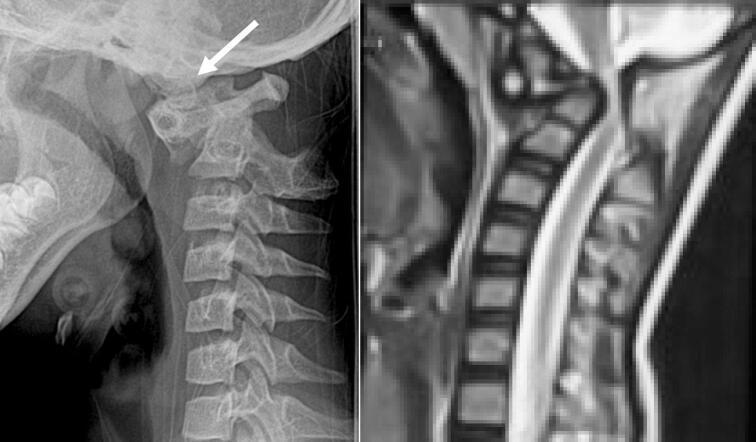

We present two cases of Os odontoideum accompanied by Down syndrome. Both patients were hospitalized due to progressive tetraparesis after falls several months prior. Upon examination, the patients exhibited myelopathy and were unable to walk or stand. MRI revealed spinal stenosis at the C1-C2 level due to atlantoaxial dislocation. C1-C2 fixation using Harms' technique was performed in both cases. One case experienced a complication involving instrument failure, necessitating revision surgery.

我们报告两例伴有唐氏综合征的齿突缺如病例。两名患者均因数月前跌倒后进行性四肢轻瘫入院。检查时,患者表现出脊髓病,无法行走或站立。MRI显示由于寰枢椎脱位,C1-C2水平存在椎管狭窄。两例均采用哈姆斯(Harms)技术进行C1-C2固定。其中一例出现器械故障并发症,需要进行翻修手术。